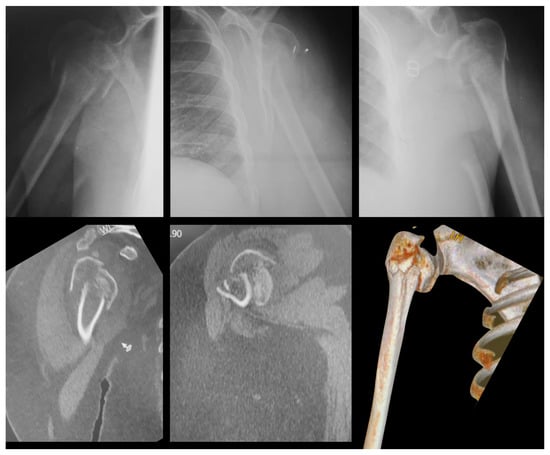

- We separated 20 cases of fractures of the proximal humerus, with X-rays and CT images, individualized in a separate folder;

- We ask that each examiner define which Hertel criteria are present by evaluating the radiographs and then their respective CT scans;

- In the folder with the files there is a photo explaining each of the 3 Hertel criteria, (reproduced from these author original article);